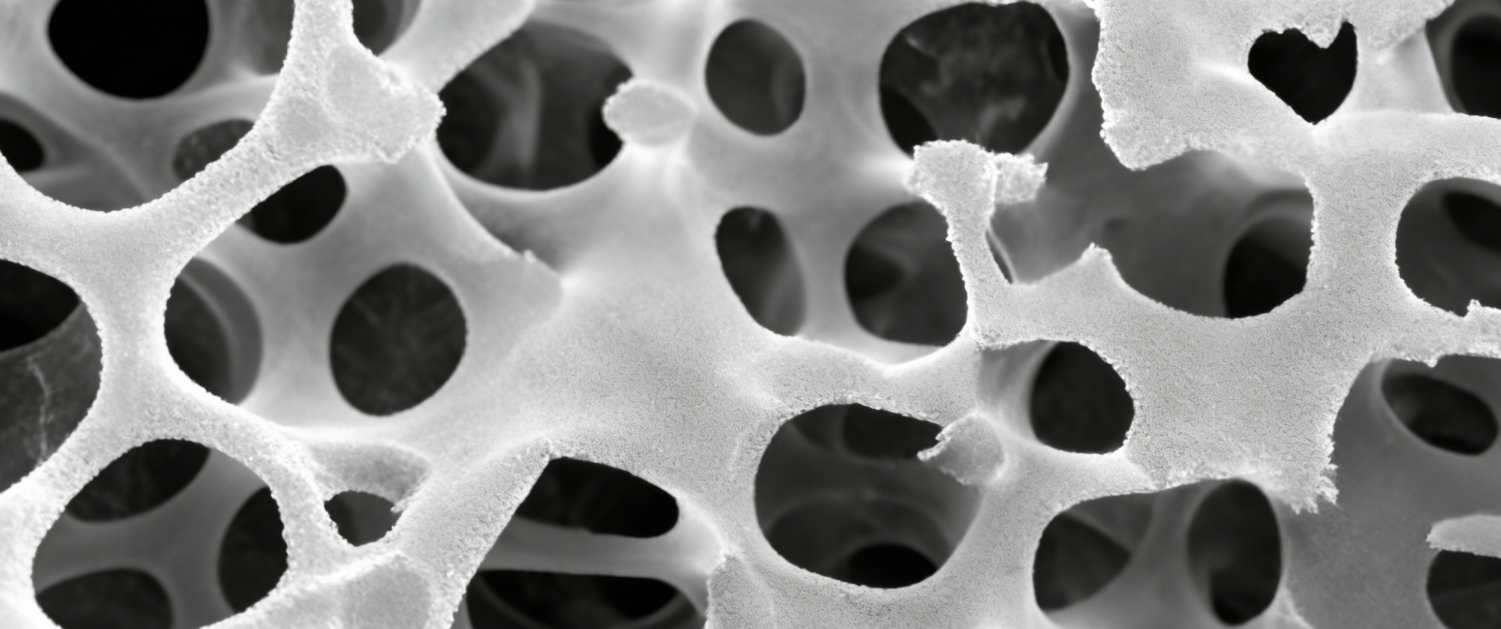

在我国高端医疗器械国产替代加速、再生医学材料快速迭代的背景下,丝素蛋白骨修复材料凭借优异生物相容性、可降解性与临床适配性,成为骨修复领域极具价值的创新赛道。湖南易天然医疗深耕这一细分领域,以全链条先发优势确立领跑地位,成为行业内率先打通“原料 — 研发 — 转化 — 注册 — 量产” 闭环、唯一启动丝素蛋白骨修复三类创新器械标杆项目的企业,成功填补国内市场空白,引领行业高质量发展。

作为细分赛道先行者,易天然医疗以战略眼光布局全产业链,构建起同行难以复制的核心壁垒。公司率先实现从原料标准化提取、核心技术研发、临床需求转化、注册申报到产业化落地的全流程贯通,打破行业单一环节布局、研发与临床脱节、量产能力薄弱的瓶颈。依托完整生态体系,企业成功启动丝素蛋白骨修复材料三类创新器械标杆项目,打通“临床需求 — 技术研发 —NMPA 注册” 全链路,以硬核实力填补国内丝素蛋白基骨修复三类器械市场空白,确立不可撼动的领跑地位。

面向临床与市场,易天然医疗以全链优势拉开与同业差距。从原料端联合国家级实验室实现全链路溯源,到研发端对标三类器械标准打造核心技术;从转化端建立临床需求导向的医工协同体系,到量产端依托二类器械产业化基础筑牢产能根基,企业形成“技术有壁垒、转化有体系、量产有能力、政策有支撑” 的发展格局。